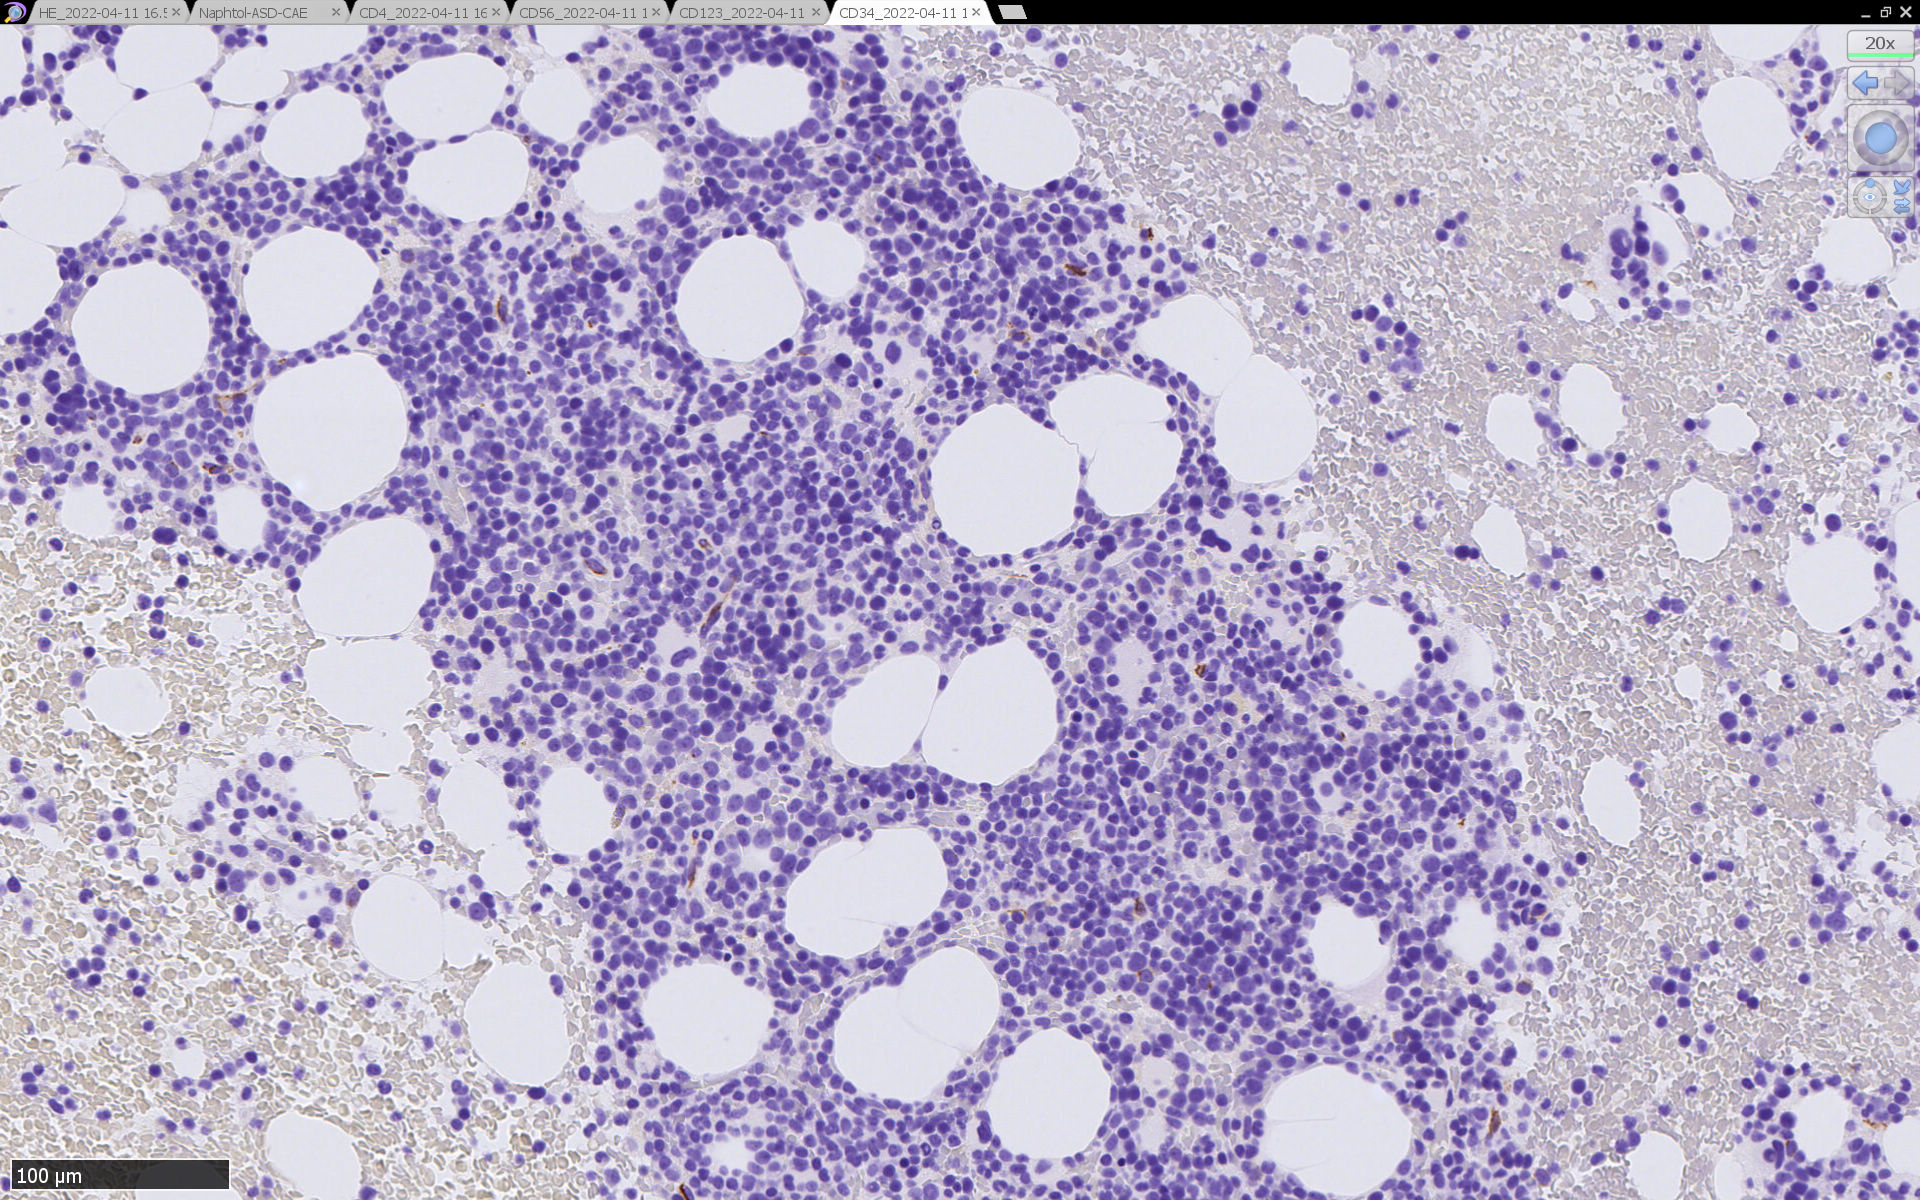

骨髄病理所見

HEでは腫瘍細胞の同定が難しい. 本症例は ASD-Giemsa染色を見ても, 腫瘍胞巣はよくわからなかった. 皮膚が先に診断がつき, 次いでBone marrowだったため, 免疫染色にすすめたが, Bone marrowが先だと診断に困ったかもしれない. 本例は, 骨髄がhypercellularで, dysplastic hematopoiesisがありMDSも疑われている.

免疫染色

CD4は染まりすぎの感がある(濃く染まる細胞はCD4+ T-cellかもしれない). CD56, CD123が陽性で可能性が高くなり, BPDCNの診断にはCD34は陰性であることが必要

TCF4、CD123、TCL1をconsultationにより染色していただき, 陽性を確認した. CD34-, lysozyme-, CD123(おいてある病院は少ないかも)をしらべて, BPDCN研究会あてconsultationをする流れでしょうか.